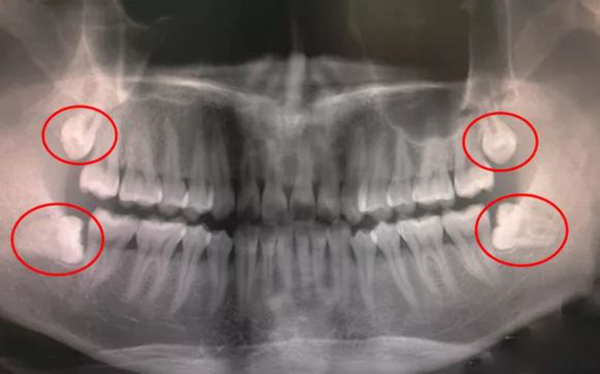

想要确认智齿是否需要拔掉,可以先去医院拍片查看正常位置,假如没什么太大问题,不拔牙实际上也没事的。

假如智齿位置比较奇怪,最终食物可能会在牙齿间残留,而智齿过于隐蔽,很容易会长出蛀牙,假如不及时拔掉可能会影响到其他的牙齿。